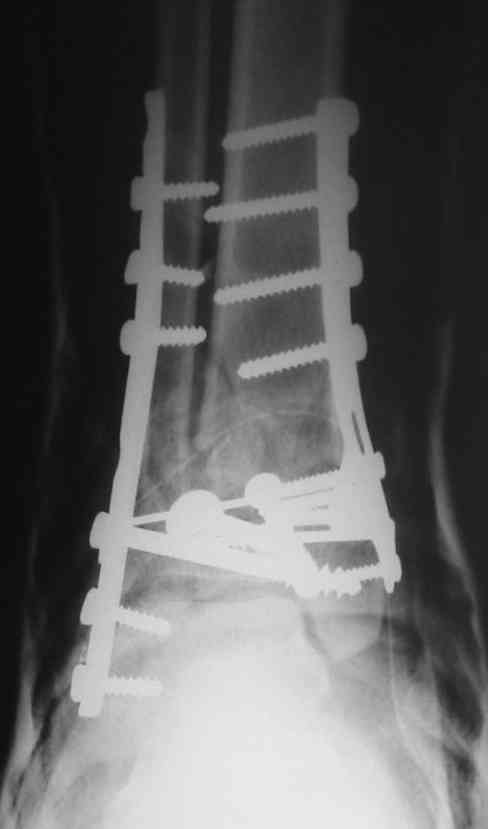

Это типичный перелом пилона, который надп лечить только открыто.Извини те что опоздал к обсуждению, но даже если вы уже оперировали больного по Илизарову это даже лучше.Посылаю картинки.

На рентгенограммах типичный перелом пилона по типу С-3. есть опыт до 100 открытых опреаций у нас в клинике. 20 примерно в год. Принцип один -все внутрисуставные переломы нуждаются в открытой репозиции и внутренней стабильной фиксации. При поступлении КТ не надо, так как получается только нагромождение костей. Истинной картины нет. Главное восстановить длину малоберцовой кости - это ключ к успеху. При поступлении меньше всего надо думать о сосудистых расстройствах, т.к. сама операция и репозиция даже сначала частичная даёт улучшение сосудитых нарушений. Причём очень быстро. Операция в 2этапа. При поступлении доступ позади наружной лодыжки, причём обязательно. После этого репозиция малоберцовой кости и фиксация пластиной 1/3 трубки под винт 3,5. Дренаж и любой аппарат наружной фиксации. Затем после спадения отёка на 5-7-10 день аппрат снимается и дугообразный разрез спереди от медиальной лодыжки 10-12 см. Главной чтобы расстояние между 1 и вторым разрезом было не меньше 7-8 см. Тогда не будет некрозов лоскутов. Таранная кость используется как матрица на неё укладываются отломки и фиксируются пицами. Ренг-контроль. Отломки лежат все отдельно, но ничего не высыпется. При переломах С-3 всегда нужна костная пластика (из крыла). Фиксация пластиной лист клевера простой или LCP. Гипс не нужен. Дренаж до 48 часов. Операция длится 3-4 часа обязательно без жгута. Посылаю примерно такой же случай.